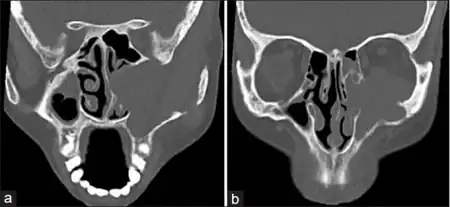

Diagnosis

Esthesioneuroblastoma can resemble small blue cell tumors like squamous cell carcinoma, sinonasal undifferentiated carcinoma, extranodal NK/T cell lymphoma, nasal type, rhabdomyosarcoma, Ewing/PNET, mucosal malignant melanoma and neuroendocrine carcinomas (NEC) that occur in the intranasal tract.[1] Compared to other tumors in the region, esthesioneuroblastoma has the best prognosis, with an overall five-year survival rate of 60–80%.[1] Fewer than 700 cases have been documented in the United States alone.[12] Esthesioneuroblastoma is characterized by neurofibrillary stroma and neurosecretary granules that are not seen concurrently by any other pathologies in the region.[1] Histological tests such as keratin, CK5/6, S-100 protein or NSE can be run to further differentiate esthesioneuroblastoma from other tumors.[1]

Staging

The Kadish classification is used for clinical classification of sinonasal tumors including esthesioneuroblastoma. Subsequent research articles have been published to determine prognosis based on tumor grade.